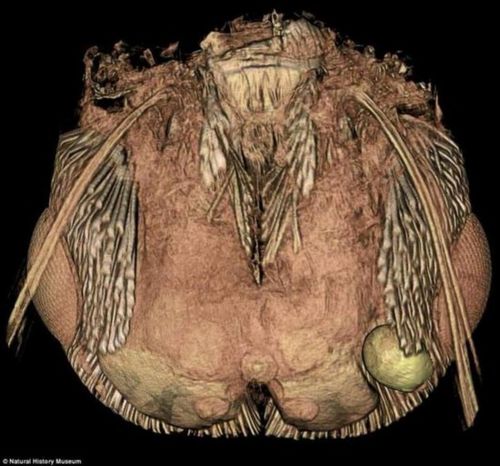

寄生虫控制大脑

吃进去的寄生虫,它可能爬呀爬,就爬到脑子里去了